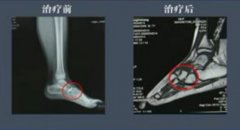

我院運用中醫整體觀,以辨證施治理論為指導,通過望、聞、問、切,四診合參的方法,探求病因、病性、病位、分析病機及人體內五臟六腑、經絡關節、氣血津液的變化、判斷邪正消長,進而得出病名,歸納出證型,有目的地選擇中藥湯劑、針灸、火療、低頻治療、膏藥進行治療。這里圖片原因不能調用,請注意